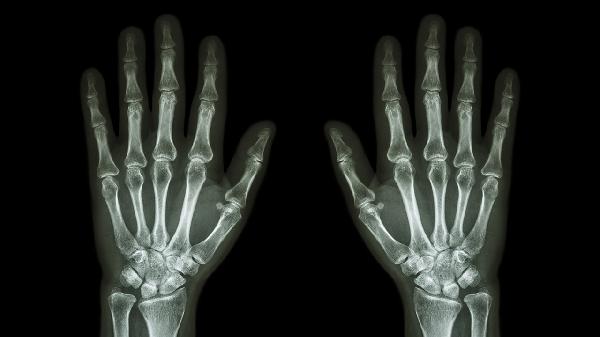

关节软骨退行性变引发的骨关节炎常见于中老年人群,可能与长期劳损有关。症状包括关节僵硬、活动时摩擦感,X线检查可见骨赘形成。治疗包括关节保护训练、局部注射玻璃酸钠,严重者需考虑关节置换术。